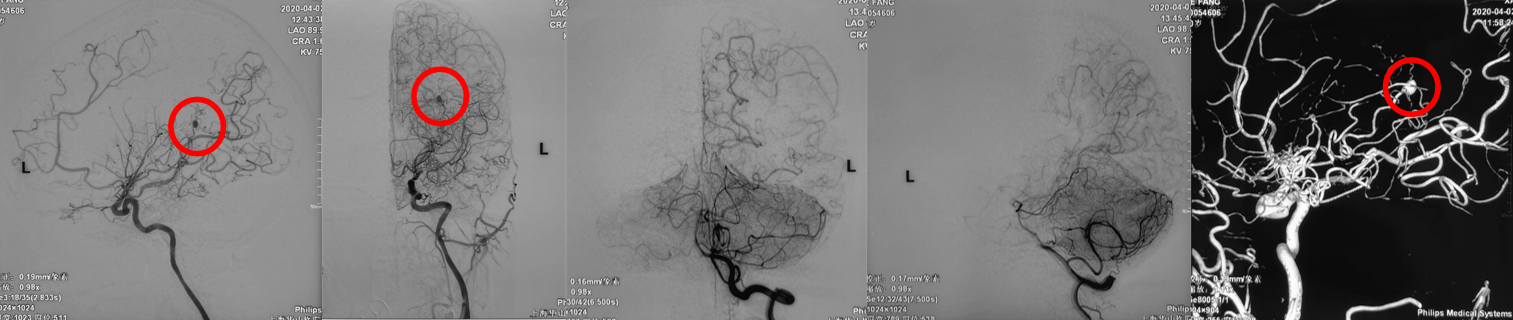

手术方案A:动脉瘤栓塞联合低流量搭桥。

手术方案B:动脉瘤切除联合低流量搭桥。

Postop dyna CT(-),GCS15,返回ICU,考虑择期行开颅手术。

有观点认为此类动脉瘤可以保守治疗,因为较小的脑室旁动脉瘤可能自发消退,但同样存在保守治疗的病例预后不佳[1-4]。深部动脉瘤通过血管内介入治疗往往能取得较好的疗效,治疗能否成功关键取决于载瘤动脉直径[5]。血管内栓塞通常是烟雾病患者脑室旁动脉瘤的首选方案,因为可以避免开颅手术对脑实质的损伤及相关的缺血事件发生[1]。在一项病例系列研究[6]中,血管内栓塞成功治疗了7例(88%)烟雾病伴脑室旁动脉瘤且无围术期并发症,其中6名患者在出院时完全康复(75%)。然而,烟雾病患者载瘤动脉往往十分迂曲,且动脉瘤容易破裂[5]因此血管内治疗往往充满挑战。显微手术夹闭是动脉瘤的传统治疗方法,但在治疗深部动脉瘤时,术中破裂的风险可能更高。微创手术如小骨窗和神经内镜已用于治疗颅内深部病变,并取得了不同程度的成功。

在本例病例中,针对脑室内动脉瘤,我们首选血管内治疗栓塞脑室旁动脉瘤,因为血管过于迂曲尝试失败。术后出现脑室内出血,于是启动备选方案,急诊在磁共振导航下通过endoport辅助进行动脉瘤切除,同时部分清除脑室内血肿并放置脑室外引流,降低远期脑脑积水的风险。随着神经内镜的普及,深部的脑血管病变的治疗方案有了更多的选择,而充分的术前评估与周全的手术方案规划是手术安全与成功的基石。